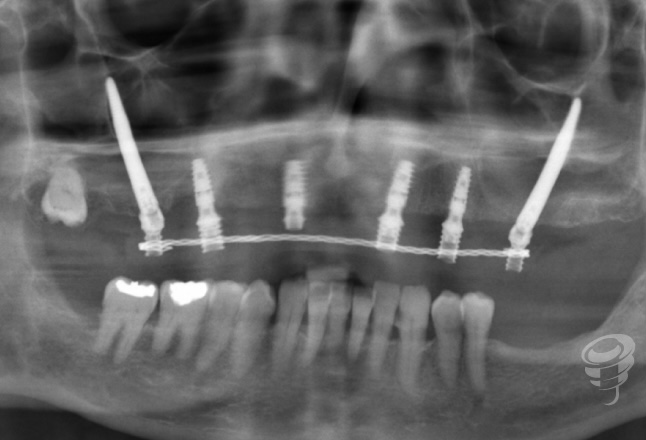

Orto postoperatorio inmediato + Carga inmediata. (Imagen 10 y 11)

Imagen 13

Orto a los 3 años de evolución + Prótesis definitiva. (Imagen 12 y 13)